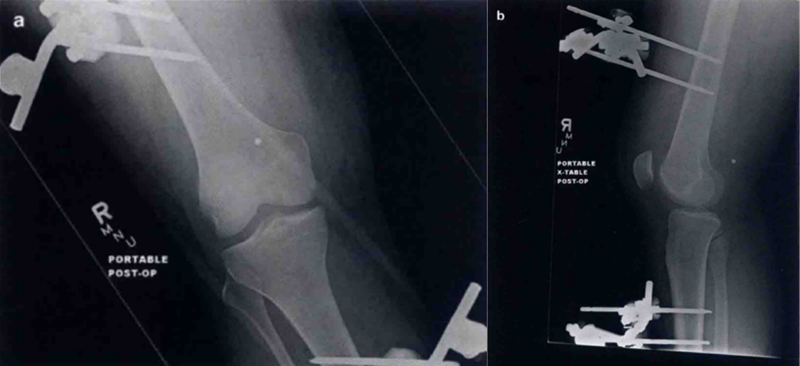

损伤能量水平在一定程度上决定了膝关节脱位的治疗过程。高能量膝关节脱位更常合并其他损伤,可能会导致治疗的延迟。我们发现对于高能量膝关节脱位,最好通过外固定支架保持患者稳定,直到其能够承受手术修复(图4)。临时固定6~8周有时可以作为那些合并严重损伤忠者的治疗选择。相反,接受低能量的膝关节脱位患者,一旦活动度有所恢复,通常适合早期重建或修复,或重建侧方结构。尽管胭动脉损伤完全可发生于任何膝关节脱位患者,但认为在低能量损伤患者中很少发生。

图4 对前后(a)侧方(b)的膝关节不稳定脱位采取跨关节外固定支架固定